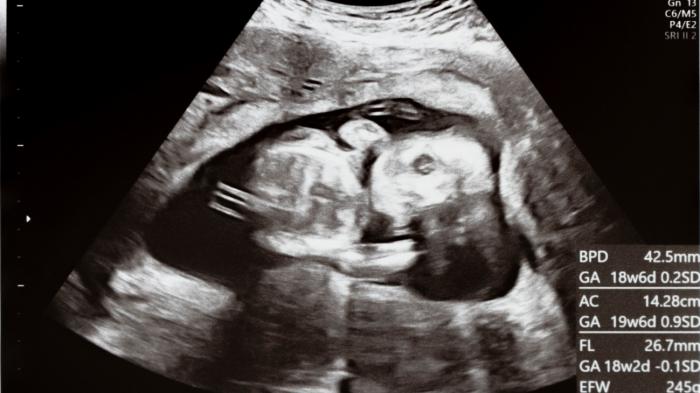

【2024】エコー写真の色褪せ・消える原因と保存方法を徹底解説!

エコー写真は、多くの方にとって大切な思い出を切り取った貴重なものですよね。しかし、色褪せや写真の全体的なクオリティが落ちてしまうこともままあります。

エコー写真の色褪せ・消える原因

エコー画像の色褪せや一部消失は、さまざまな要因が関与しています。主な原因としては、アナログ写真ならではの劣化のほか、保存方法、元の写真のクオリティに左右されます。これらの要因により、エコー画像が薄れたり、消えたりすることがあるのです。